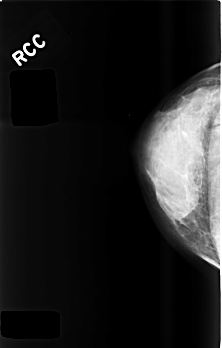

C_0477_1.RIGHT_CC

RIGHT_CC LINES 4520 PIXELS_PER_LINE 2880 BITS_PER_PIXEL 12 RESOLUTION 50 NON_OVERLAY